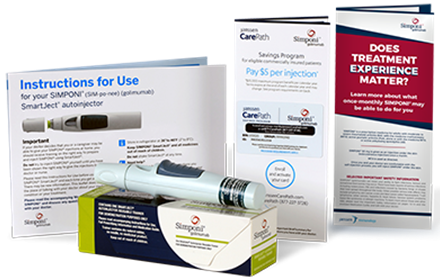

God effekt av diabetesvaccin

27 May 2021

Medlet som bromsar processen mot typ 1-diabetes